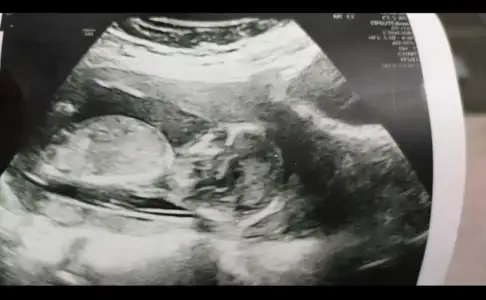

Erkek gibiEki Görüntüle 2710257 Banada tahmin yaparmisiniz lütfen![]()

Erkek gibi geldi canimmBnada yorum yapar Muş’un cnm

Erkek gibi geldi canimm![]()